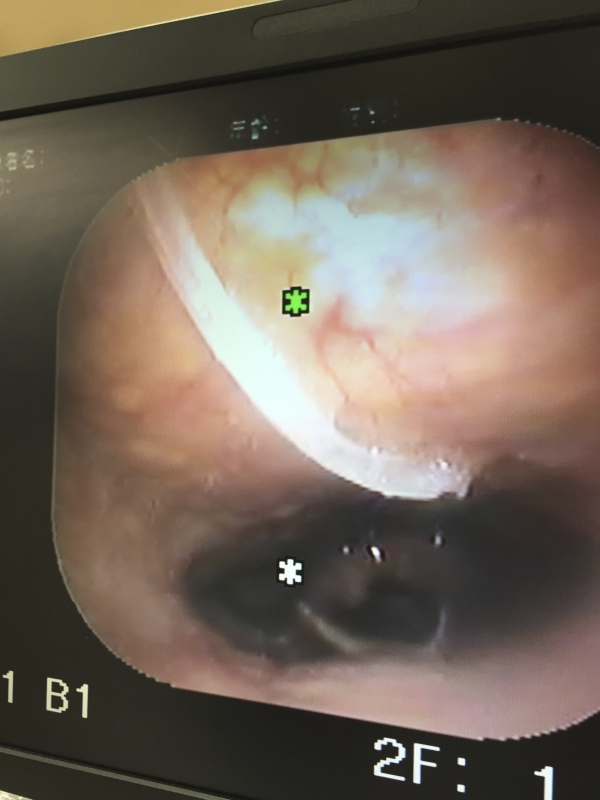

直視では見えず、喉頭鏡を覗いた主治医は「コリャ、太か骨ねぇ〜!!ナンバ喰うたらこぎゃん骨が喉に突きササッとですか?!」と小生に尋ねられたんですが小生の鼻は喉頭鏡で塞がれておりますのでまともに話す事はできません。。。 でっ、結局、局所麻酔下の下、喉頭鏡を用いた異物(=魚:イサキの骨w)除去術を敢行したのでありました。。。

口から飲み込んだイサキの骨は小生の右鼻から出てきましたがイサキの骨は小生の喉に20mm「ぬかって」おりました。。。 主治医が看護師に「鉗子ば緩めたらイカンケンね!!放すなよ!!」と恐ろしい事を言っておられた事は聞き逃しませんでした。。。泣

写真は除去できましたイサキの骨と大きな骨に見入られた耳鼻科の主治医がデジカメで「イサキの骨!!」を写メしているお姿を写メ返ししている模様と喉頭鏡で小生の喉にイサキの骨が突き刺さっている様子であります。。。